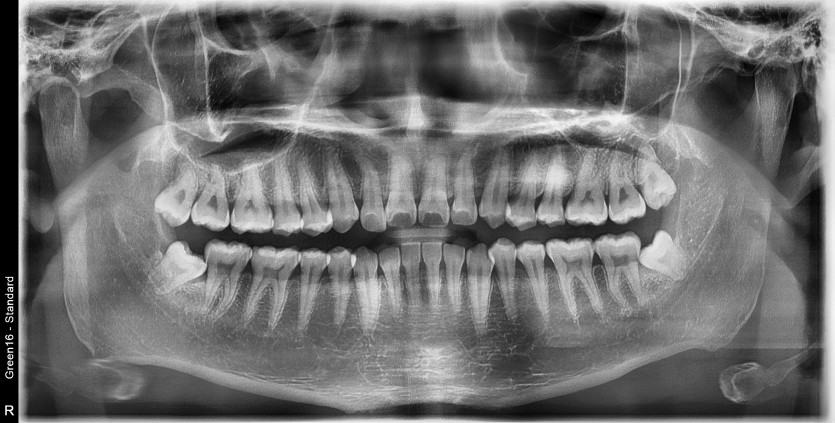

#18,48 사랑니 발치

구강 외과 전문의가 당일 발치했습니다.